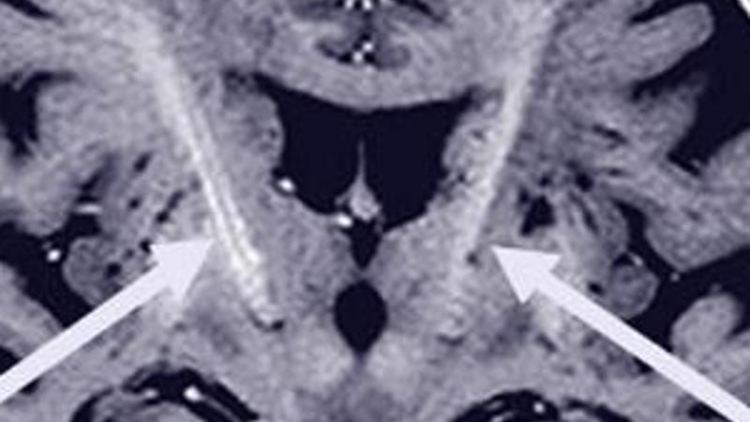

Bei Parkinson fallen Nervenzellen aus, die das für Bewegungen wichtige Dopamin bilden. Elektroden stimulieren diesen Bereich und können so die motorischen Störungen lindern. Foto: Universitätsmedizin Kiel